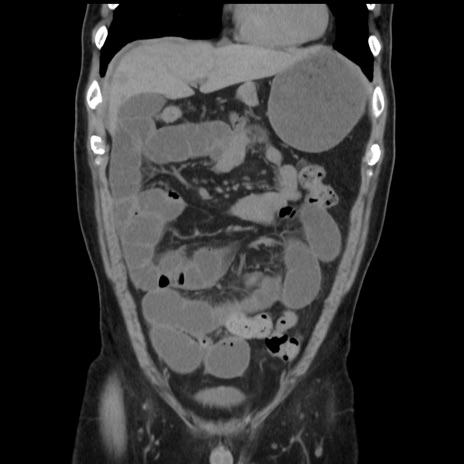

症例16(冠状断像)

【現病歴】 約1ヶ月前より間欠的に腹痛と嘔吐あり、当院消化器内科を受診したところCTで多発する肝臓のLDAを指摘され、精査中であった。以降は消化器症状は安定していたが、2日前より嘔気と腹痛があり、同日より排便・排ガスが消失した。改善認めず、 本日、救急外来を受診した。

【身体所見】意識清明・会話良好、BT 36.3℃、BP 127/80mmHg、 P 80bpm、腹部:膨満あり、平坦・軟、上腹部正中および下腹部正中に圧痛あり、反跳痛なし、筋性防御なし。